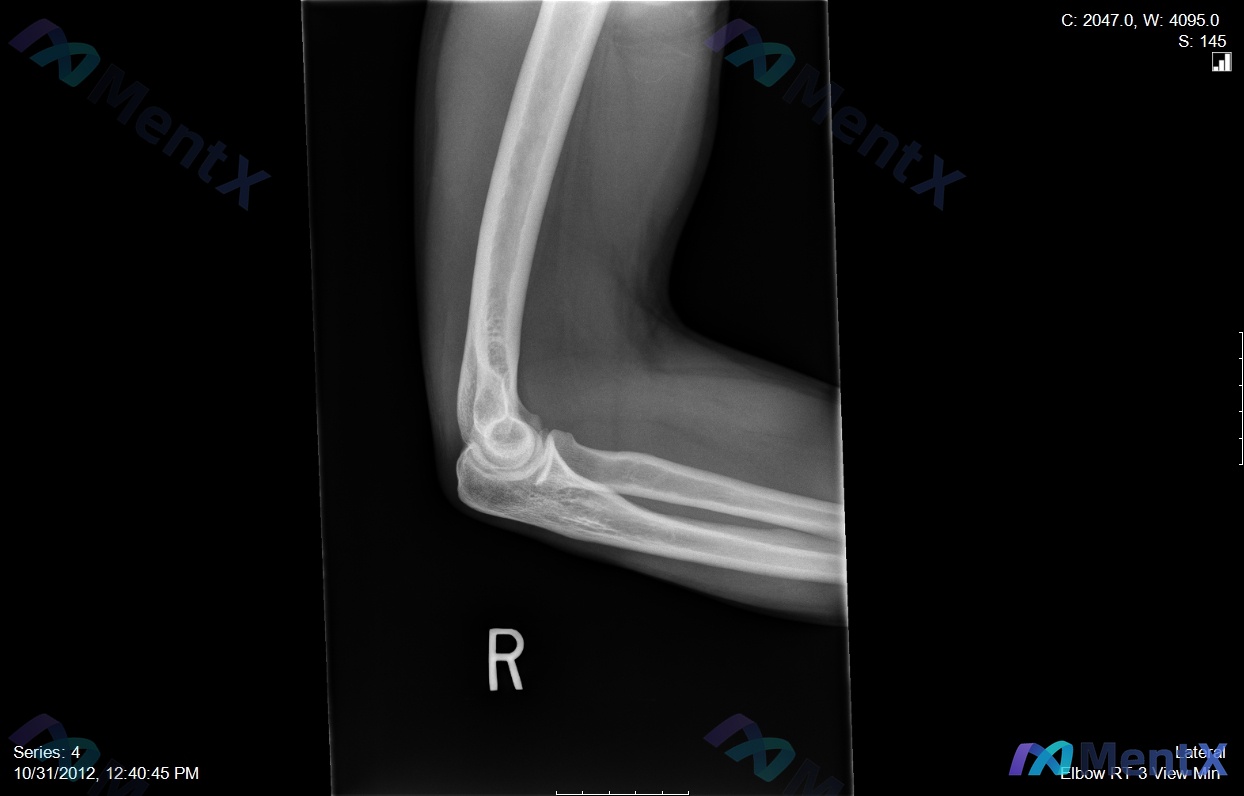

整理了一个挺有警示意义的病例,核心是「别被带偏,抓死核心体征」—— --- 病例基本情况 - 患者:35岁男性木匠 - 主诉:右肘前窝疼痛,用螺丝刀时明显加重 - 病程:6个月+,规范保守治疗(休息、抗炎、理疗)无效 关键体格检查 这个是破局核心: ✅ 钩试验(针对桡神经浅支卡压)正常 ❌ 但抗旋后...